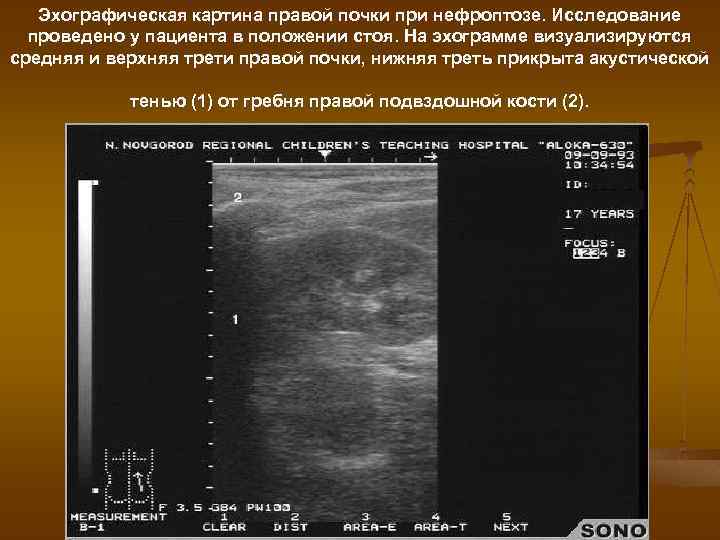

Эхографическая картина правой почки при нефроптозе. Исследование проведено у пациента в положении стоя. На эхограмме визуализируются средняя и верхняя трети правой почки, нижняя треть прикрыта акустической тенью (1) от гребня правой подвздошной кости (2).